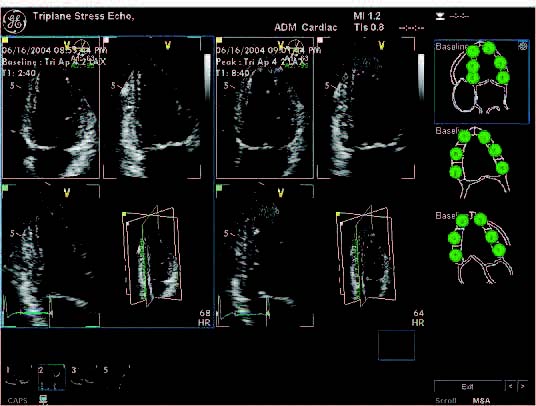

- Stress Echo

- Quantitative stress analysis